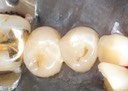

Joe Cha #3 prep